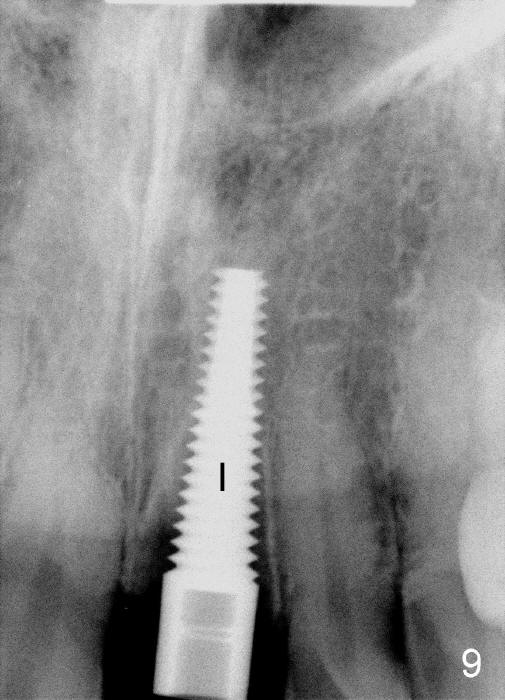

The upper right central incisor (Fig.1: #9) fractures subgingivally due to trauma for a 40-year-old man. The incisive canal is large (I) and close to the root of the central incisor. After extraction, the osteotomy (Fig.3b, 4: O) is made with 2 mm pilot drill (Fig.2: D) on the lingual wall (Fig.3a: L) of the socket (Fig.3a: S). To push the incisive canal mesially, the osteotomy is enlarged by 3.5x21 mm and 4x21 mm tapered osteotomes (Fig.5,6: O). Due to the lingual slope (Fig.7a arrow), the osteotome (blue outline) starts to deviate bucally. To reduce this tendency, the coronal portion of the lingual slope is removed (Fig.7b: yellow circle). The final implant (4.5x20 mm) is able to be placed as lingually as possible (Fig.7c, 8).

Bone expansion allows the implant (Fig.9 I) to have primary stability (insertion torque between 50 and 60 Ncm), since the cortex of the incisive canal is apparently intact. Allograft is placed in the labial gap (Fig.10, 11 *) following installation of the abutment (A). Finally an immediate provisional (Fig.10,12 P) is cemented. Fig.13,14 are taken 8 days postop. The patient returns 3 months postop (Fig.15,16). Osteointegration appears to have occurred (Fig.15 arrowheads) and is more obvious 9 months postop (Fig.17).